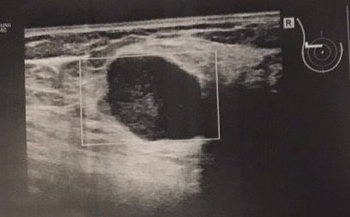

Zwei Tage später lag ich wieder auf der Liege am Ultraschall. Diesmal hatte ich mir eine günstigere Blusenfarbe ausgesucht. Als Mutter ist man erprobt, wie man mögliche Flecken verschwinden lässt. Dieses Mal war das Gesicht meines Gynäkologen gar nicht mehr so pokerhaft. Diese runzelige Stirn sah mehr nach einem verlorenen Match aus, aber ich überbrückte die Zeit mit lässigem Smalltalk, ohne dass mein Blick von den Stirnfalten abließ. „Es ist keine Zyste. Es ist durchblutet. Das spricht für einen Tumor“ Stille im Behandlungsraum. „Ob er gut- oder bösartig ist, müssen wir im nächsten Schritt testen“. Sein Blick strahlte Zuversicht aus- und gleichzeitig Sorge.

Einerseits hätte ich mir diesen Termin sparen können, denn es bildete nur ab, was ich schon wusste. Es zeigte einen Tumor, nicht aber, ob es tatsächlich Krebs war. Ich wurde noch zur Mammographie und zum Ultraschall geschickt- und obwohl ich mit den Nerven am Ende war, stieß ich hier auf einen Arzt, der mich verstand. Sofort nahm er eine Stanzbiospie und schickte sie per Express ins Labor.